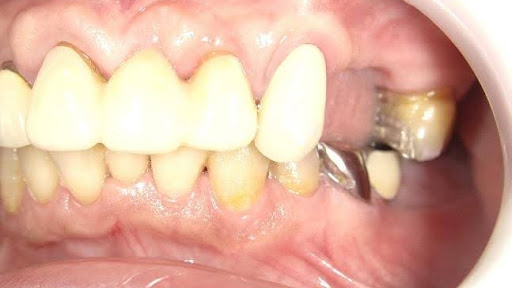

Before

枚方市のインプラントの症例

After

M・I 様 女性 70代

症状としては、左下56は、歯周病で欠損したと考えられるが、かなりの骨欠損をともなっていた。左上456に関しては、動揺が大きく、炎症が起き、排膿、および、歯性上顎洞炎を起こしていた。

治療法としては、動揺がひどくなってきて、炎症の症状もあったため、左上56の抜歯を希望。インプラント治療をその後、希望したため、左上4に関しては抜歯即時埋入。左上6に関しては、既存骨1から2mmでインプラント治療が厳しい状態であったが、グラフトレスサイナスリフトを行い、治療期間5か月はかかるということを説明して、インプラント埋入をおこないました。その後、2か月半後、大幅に骨が欠損している下顎56に対して、ショートインプラントを使用して、下顎神経の損傷を避けて、インプラント埋入を終えています。その後2か月後に光学印象で印象を行い、上顎刺億456歯、3ユニットのジルコニアブリッジを装着。下顎左側56に関しては、骨欠損が大きいため、歯冠長がだいぶ長くなるため、ジルコニアの連結冠を装着して治療を終えた。

治療結果は、上顎6に関しては、既存骨が少なく、厳しい治療ではありましたが、5か月で治療を終え、患者様の負担を最小限に抑えるができたと考えます。(従来のサイナスリフトでは、このようなケースでは1年以上、1年程度の治療期間がかかるか、治療が不可能と言われるケースだと考えます。)また、下顎は骨欠損が大きく、下歯槽管のリスクが起きることが考えられますが、ショートインプラントを使用することで安全に治療を行うことができました。

治療の期間・回数:治療期間5か月(上顎456 3ピースブリッジの治療は5か月(上顎既存骨が2mm程度しかなく、骨結合に時間がかかるケースであったために、5か月の治療期間が必要であった。)(左下56に関しては2か月半で治療を終えています。)治療回数は、13回。

治療の価格:1,474,000円(税込)

治療費の内訳:左上46および左下56のインプラント基本料(フィックスチャー及び手術費用、投薬費用、レントゲン費用、インプラント上部費用(アバットメントおよびジルコニアクラウンの費用用)330000円(税込み)×4本分 1320000円(税込)。左上5ジルコニアポンテック費用88000円(税込)。オプション費用、左上4抜歯即時埋入加算(人工骨費用を含む)+グラフトレスサイナスリフト費用 33000円(税込)、左上6グラフトレスサイナスリフト費用 33000円(税込)

治療のリスクや副作用:手術後に、痛みや腫れ、出血、合併症などを引き起こす可能性があります。噛む感覚がご自身の歯と異なる場合があります。見た目がご自身の歯と異なる場合があります。手術後にメインテナンスを継続しないと、インプラントが抜け落ちる可能性があります。